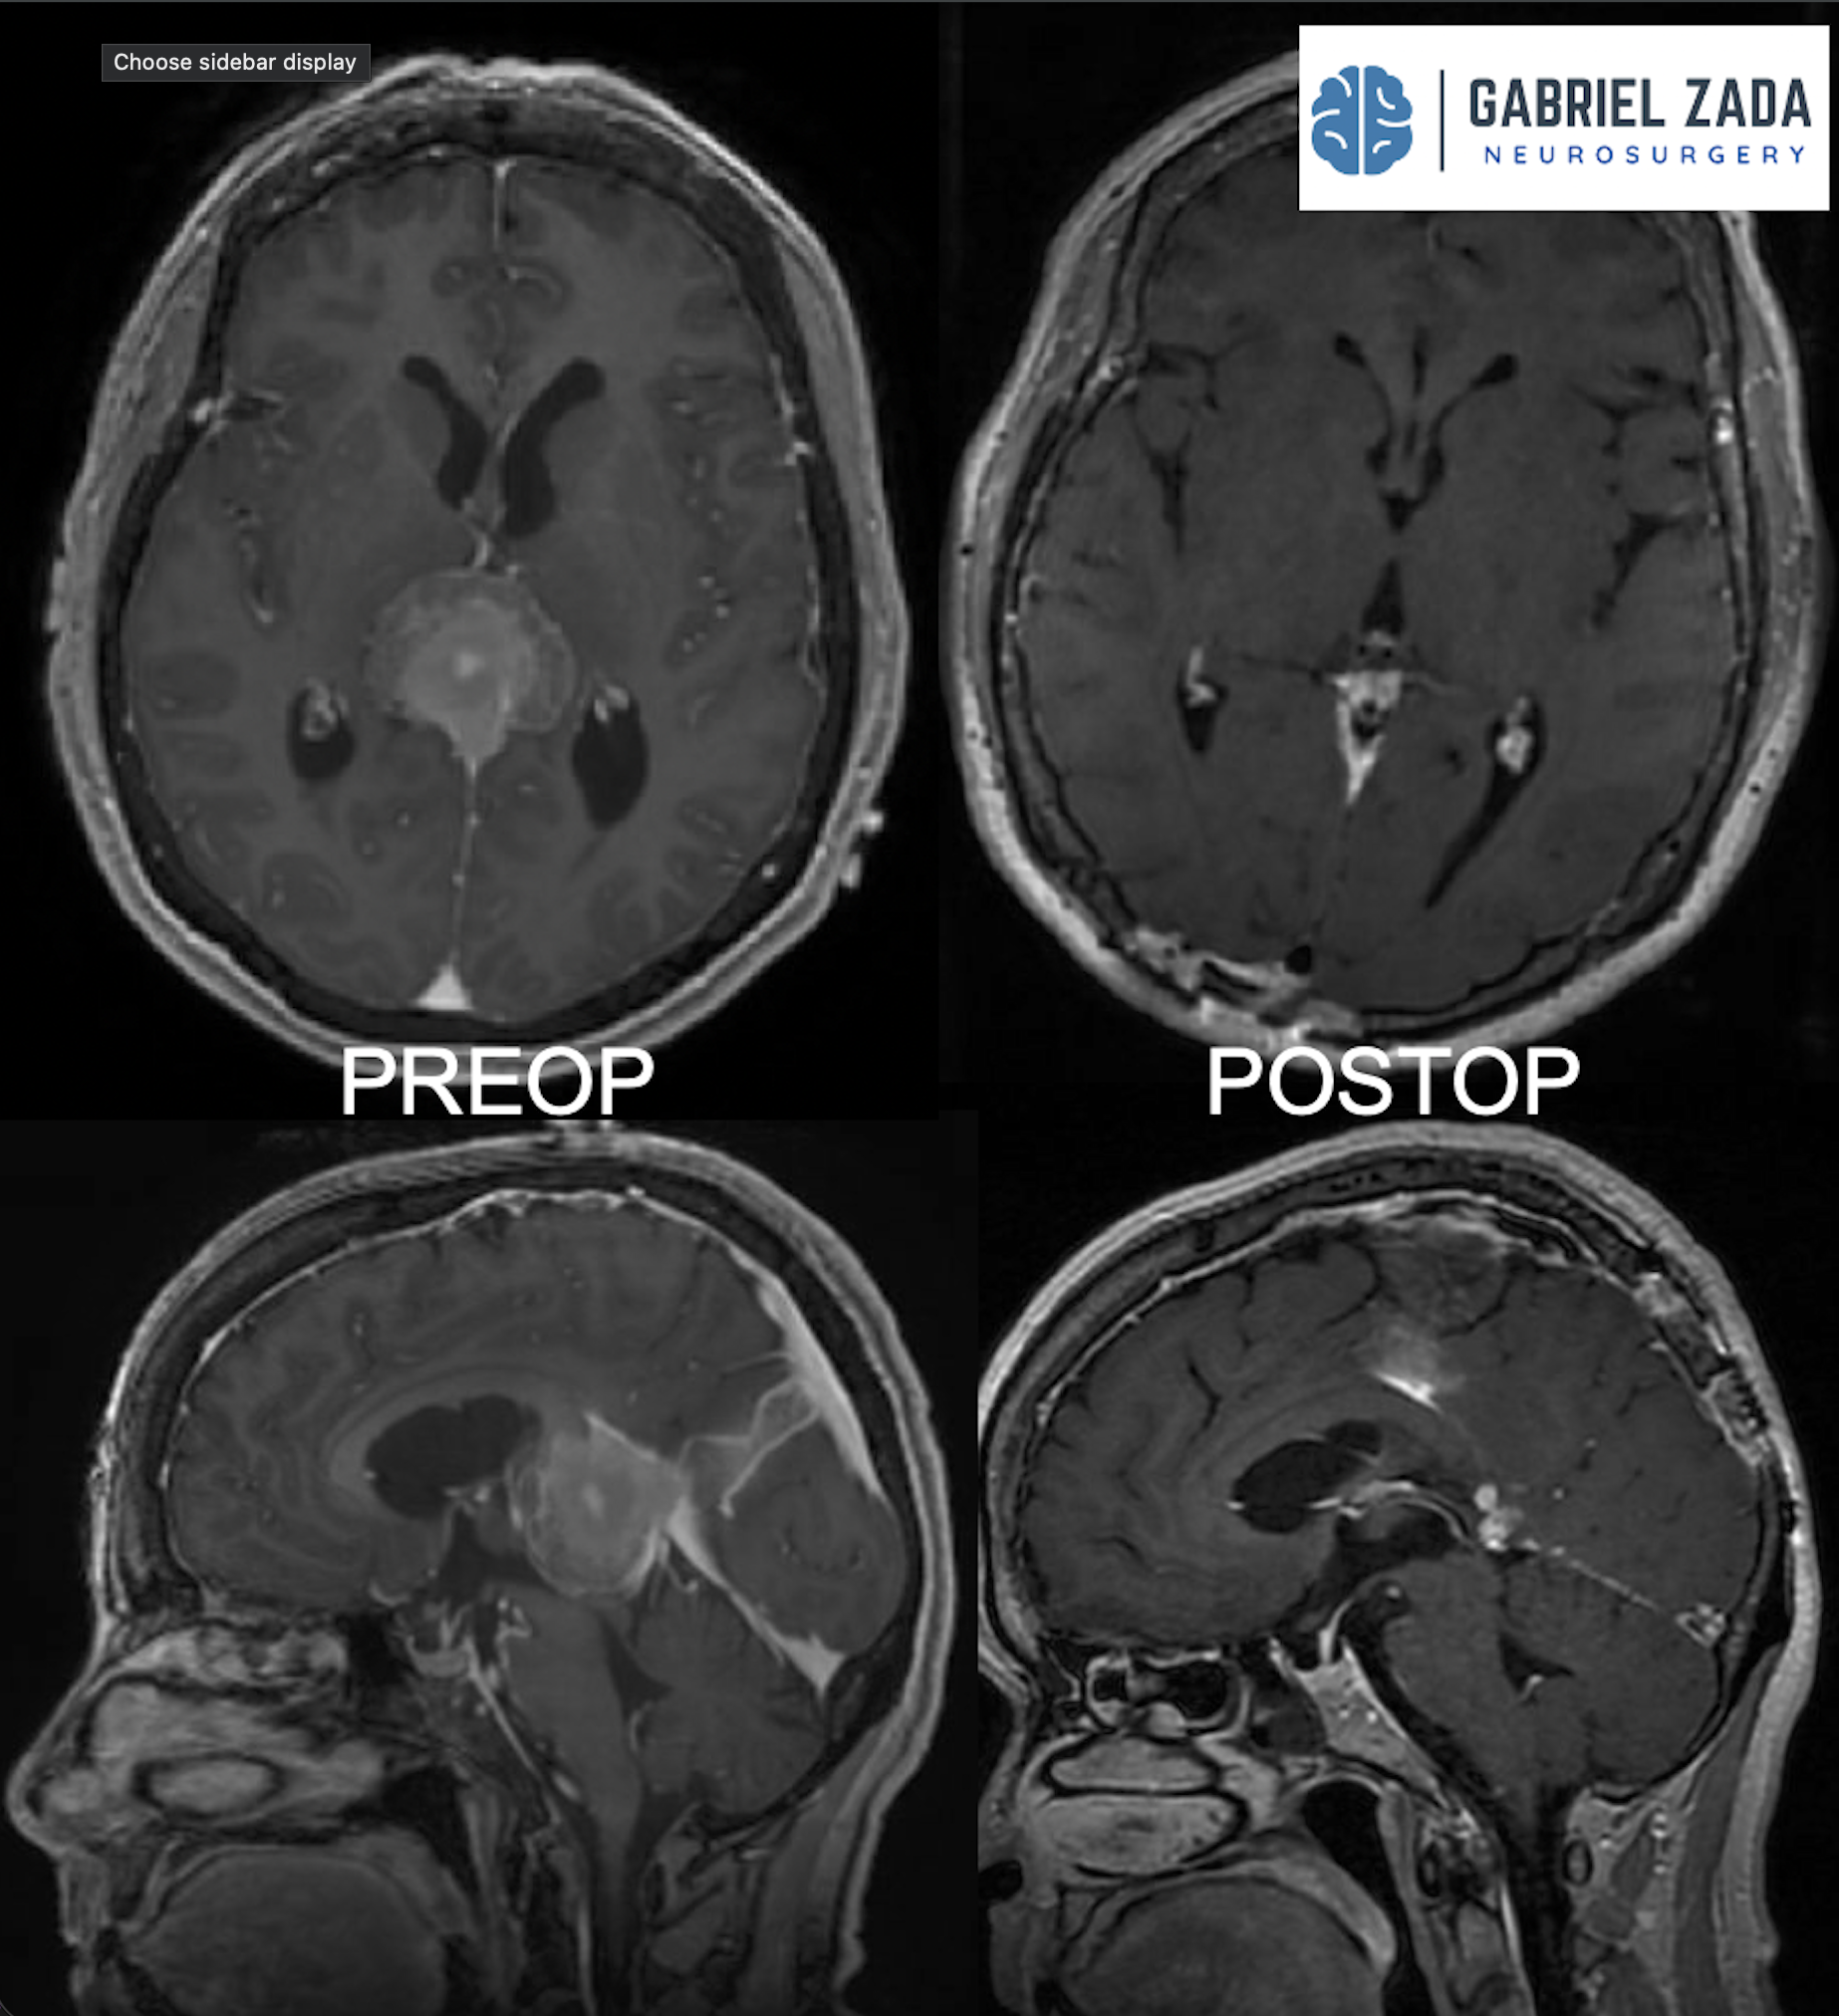

Explore this comprehensive gallery featuring pre‑ and post‑operative imaging of patients with skull‑base tumors treated by Gabriel Zada, MD, MS, FAANS, FACS. These cases highlight Dr. Zada’s expertise in advanced neurosurgical techniques and outcomes.

*Representative cases shown for educational purposes. All images de-identified. Individual results vary.